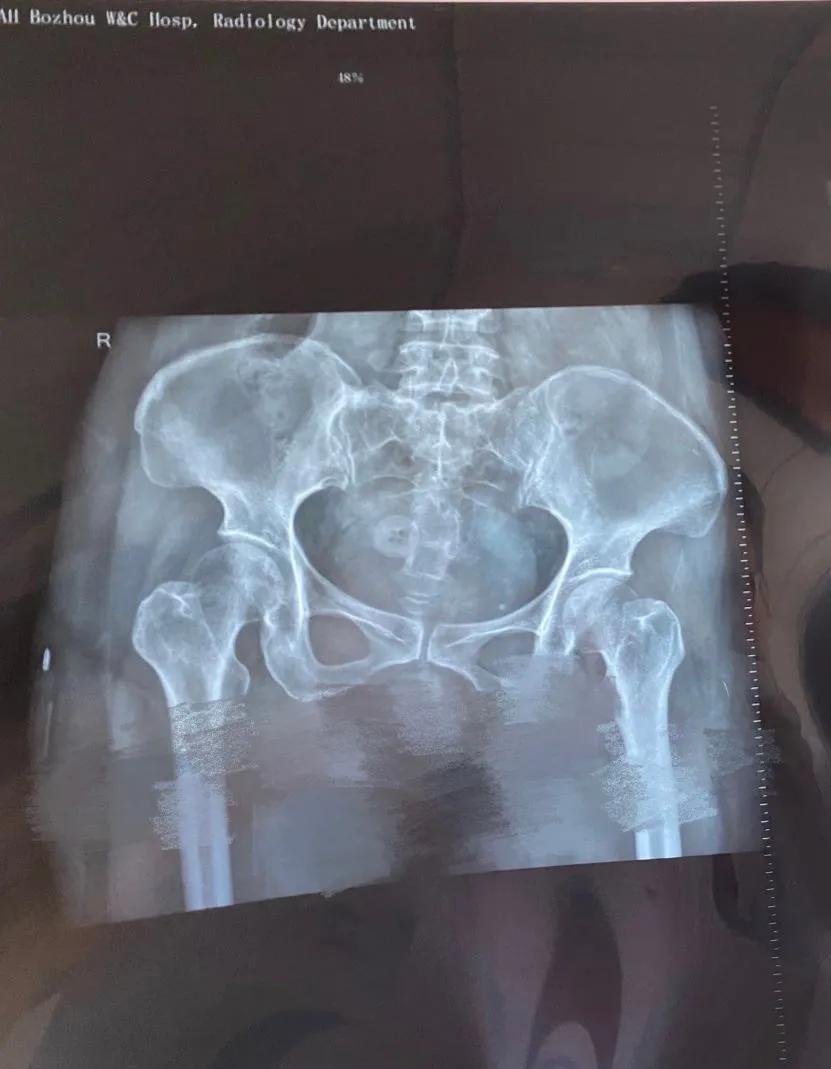

术前经过精细检查,结合超声和定位X线平片,我们判断残留节育器约3厘米,嵌顿于子宫肌层内,科室讨论后决定手术方式为经宫腔镜节育器取出备腹腔镜监视。由安医二附院专家范懿隽主任及王青元医生亲自主持宫腔镜检查+镜下残余节育器取出术。宫腔镜下见近宫腔中段处可见一实性隔样组织将宫腔分为上下两部分,宫腔内外全不可见外露的金属,这种情况下常规盲操作是无法探及节育器的。置入宫腔镜专用剪刀,直径仅0.5毫米,剪开覆盖于金属环表面的内膜组织,见断裂金属环,两端深深插入两侧壁肌壁间,同时导致宫腔内形成纤维束状粘连。微型剪刀分离两侧壁纤维束状粘及环表面黏膜完全暴露残余环。取环顺利,用时短,术中出血极少,患者及家属非常满意!